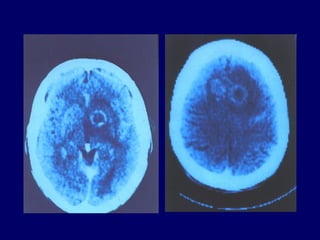

* La   neurotoxoplasmose +++

- souvent focalisée (abcès cérébraux),

- la forme encéphalitique pure:

toxoplasmose cérébrale,l’imagerie +++

- scanner : hypodensité avec prise de contraste

annulaire ou nodulaire.

multiples dans les 2/3 des cas.

- si scanner normal ou en cas de doute,

l’IRM (lésions d’un Ø < au cm) : mise en

évidence des lésions multiples alors que le

scanner peut n’avoir montré qu’une seule

lésion.

 Clinique + l’imagerie: diagnostic de présomption.

Une réponse favorable au traitement viendra à

postériori confirmer le diagnostic.

 La sérologie est peu informative.

Elle est positive avec des IgG chez la plupart des

malades atteints de toxoplasmose cérébrale.